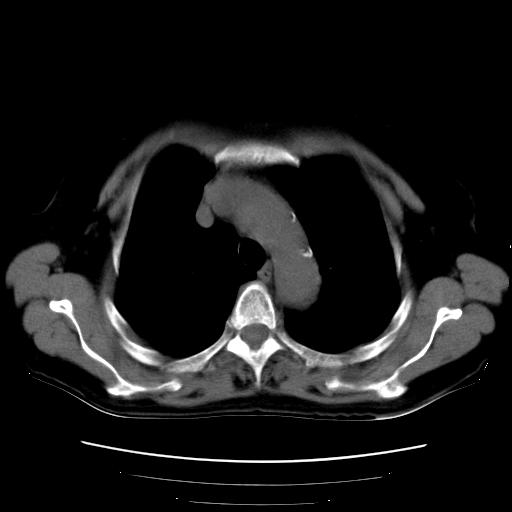

以下是引用卜一在2007-9-18 14:41:00的发言:[br]右肺肿块:毛刺+胸膜凹陷征+供血血管+浅分叶+强化。支持:周围性肺癌 !另:左侧甲状腺腺瘤!

以下是引用夏季在2007-9-18 11:00:00的发言:[br]1。右肺肿块,周围有短毛刺,肺门侧有血管与其相连,胸壁侧有胸膜凹陷征,考虑周围性肺癌 2。左侧甲状腺软组织肿块,内有高密度钙化灶,考虑左侧甲状腺腺瘤。